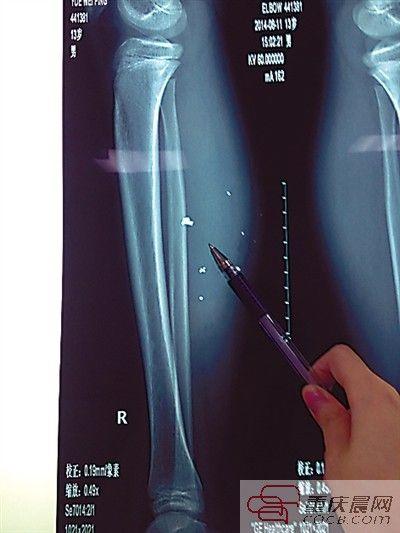

平平的小腿内异物清晰可见。

第二天,伤势过重的平平转院至儿童医院,骨科医生周悦航说,经检查,平平右小腿肿胀明显,发现有爆炸伤伴异物残留,后侧可见两处1厘米裂口,伤口较深,约1.5-2厘米。通过X光片可见患儿右小腿皮下多处高密度影,即手机爆炸后进入小腿的异物,大约10处,需通过手术取出。